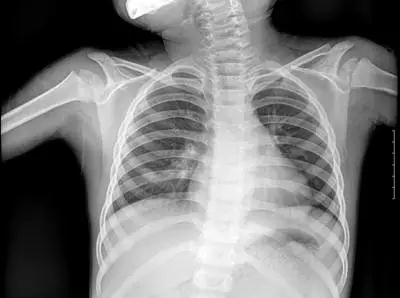

▲X射線成像圖

骨骼、鈣化灶、體內(nèi)液體等(聽起來(lái)質(zhì)地較厚重的組織),吸收X光較多,因此形成白色影像,也就是傳說(shuō)中的“高密度影”,上圖的上臂、肋骨就是如此。呼吸道、胃腸道、脂肪組織(聽起來(lái)質(zhì)地較疏松),吸收X光較少,在片子上呈現(xiàn)黑色影像,即“低密度影”,圖中含氣體較多的肺臟是代表。再就是密度居中的實(shí)質(zhì)器官、肌肉、結(jié)締組織,比如心臟,在片子上呈現(xiàn)的影像介于黑白兩色之間。X光片“涇渭分明”的特點(diǎn)幫醫(yī)生辨別身體的不同病變。骨折、肋骨病變,密度高的骨骼白色影像哪里出問題一目了然,比如液氣胸等肺部及氣道病變,肺臟的黑色影像中就會(huì)混入明亮的白色。